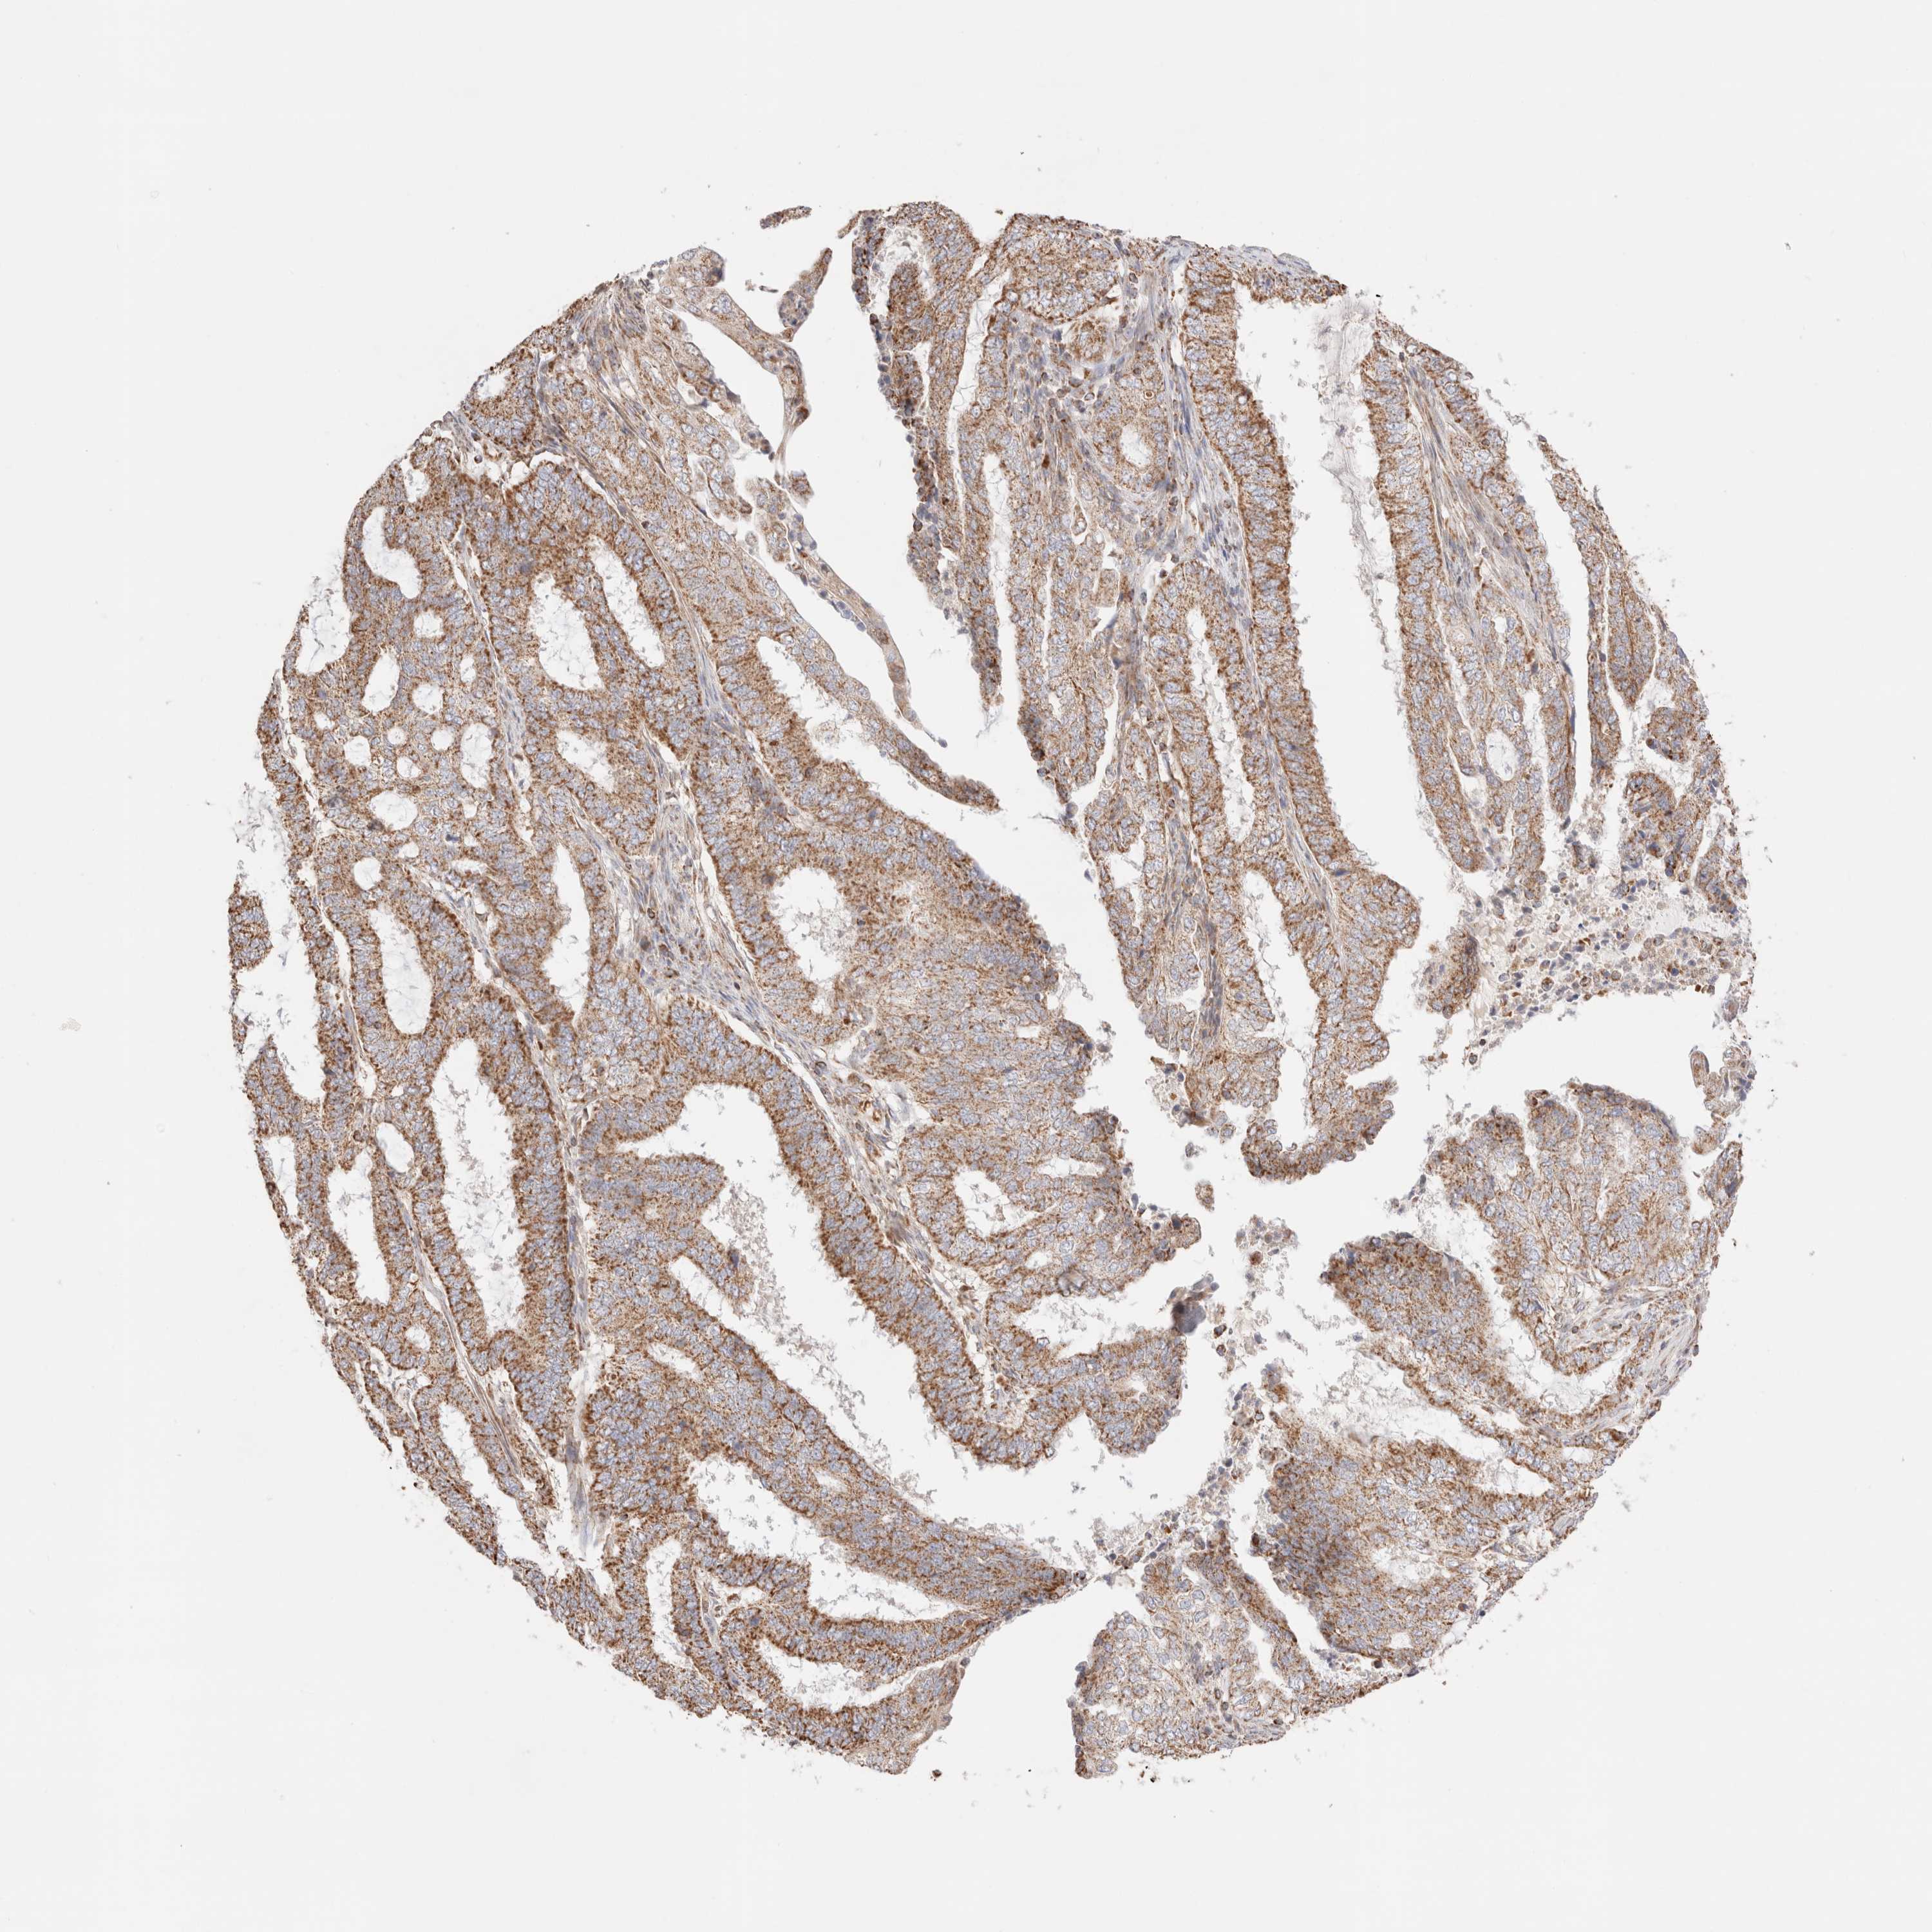

ENDOMETRIAL CANCER - Protein expressioni

A mouse-over function shows sample information and annotation data. Click on an image to view it in a full screen mode. Samples can be filtered based on level of antibody staining by selecting one or several of the following categories: high, medium, low and not detected. The assay and annotation is described here.

Note that samples used for immunohistochemistry by the Human Protein Atlas do not correspond to samples in the TCGA dataset.

Antibody stainingi

Antibody staining in the annotated cell types in the current human tissue is reported as not detected, low, medium, or high, based on conventional immunohistochemistry profiling in selected tissues. This score is based on the combination of the staining intensity and fraction of stained cells.

Each image is clickable and will lead to virtual microscopy that enables deeper exploration of all samples and also displays staining intensity scores, fraction scores and subcellular localization as well as patient and tissue information for each sample.

Antibody HPA027019

Staining

High

Medium

Low

Not detected

Intensity

Strong

Moderate

Weak

Negative

Quantity

>75%

75%-25%

<25%

None

Location

Nuclear

Cytoplasmic/membranous

Cytoplasmic/membranous,nuclear

Adenocarcinoma, NOS

Adenocarcinoma, metastatic, NOS